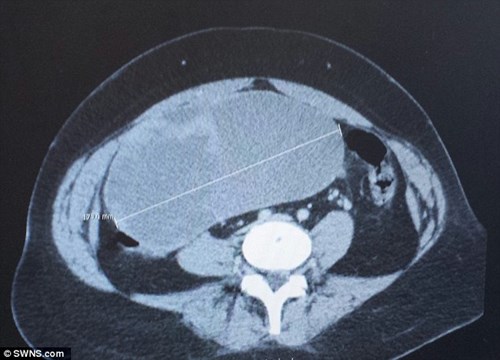

(Sức khỏe) - Emma Brown có một khối u khổng lồ có kích thước dài 173,6 mm và rộng 160,3 mm, tương đương với kích thước và hình dạng như một quả bóng bầu dục.

Khối u to như quả bóng bầu dục trong tử cung.

Các bác sĩ đã tiến hành kiểm tra và bị sốc khi thấy kích thước buồng trứng bên phải của cô tăng lên bất thường, một khối u khổng lồ có kích thước dài 173,6 mm và rộng 160,3 mm, tương đương với kích thước và hình dạng như một quả bóng bầu dục.

"Hình ảnh scan đã làm tôi bị sốc nặng, tôi chưa từng thấy khối u nào to đến vậy, tôi đã rất sợ hãi", cô Emma Brown chia sẻ.